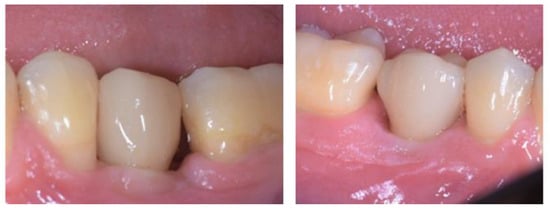

2.5. Individual Cases Description

- Case 1:

- Case 2:

- Case 3:

- Case 4:

- Case 5:

3.1. Clinical Results